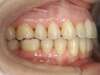

Avant

Après